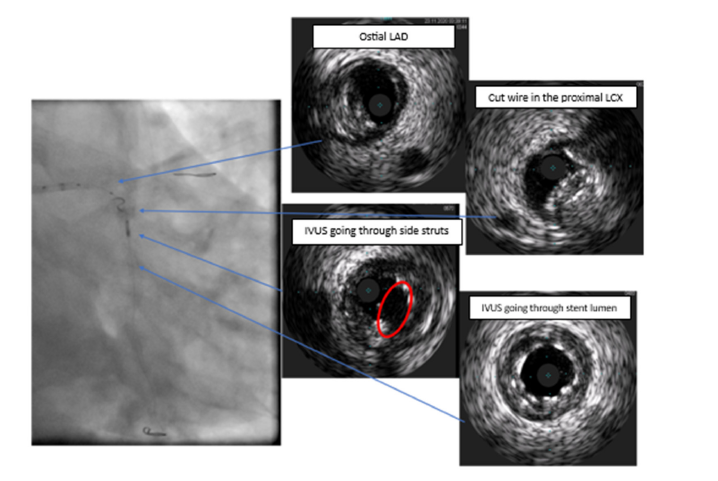

A Sion guidewire was then steered across the LCX stent with Corsair support, and predilation was performed using a 3.5×15mm Sapphire II NC balloon; however, a subsequent IVUS pass demonstrated the wire had passed behind the stent struts across a crushed proximal segment. The team elected to completely crush the compromised stent and stent across from the LM into the LCX. Still, even a low-profile 1.5mm balloon could not be advanced, and a GuideLiner could not be delivered alongside the LAD wire within the 6 F guiding catheter. While attempting to advance the Corsair, the microcatheter adhered to the LCX wire, and LCX access was lost. High-magnification fluoroscopy and IVUS then revealed a spiraling collapse of the proximal LCX stent struts-consistent with a rare geometric configuration we term the Swiss Roll Effect (see (Figure 1) for the fluoroscopic/IVUS appearances, and (Figure 2) for representative IVUS frames). Access was upsized to a 7F femoral approach. A Sion Black wire, supported by a Turnpike LP microcatheter and a GuideLiner, was advanced by tracking along the trapped wire within the rolled, crushed proximal LCX segment and into the distal LCX stent lumen, as confirmed by IVUS. The Sion Black was exchanged for a Grand Slam wire to improve support.

Figure 2:IVUS imaging of the swiss roll effect. Intravascular Ultrasound (IVUS) images showing spiraling collapse of stent struts at the proximal LCX. The digital arrows mark the inward folding and luminal obstruction at the side branch ostium, consistent with the Swiss Roll Effect.